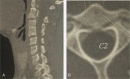

Atypical Hangman fractures (AHF) were first formally reported and considered to be more often associated with neurologic deficit in 1993. However, there is a paucity of literature focusing on these fractures. The purpose of the retrospective study was to introduce a new classification scheme for AHF and its application.Sixty-two patients with Hangman fractures were identified. There were 46 (74.2%, 46/62) AHF patients, including 29 type I, 9 type II, 5 type IIa, and 3 type III fractures (Levine-Edwards classification). Based on fracture patterns, incidence, and their impact on neurologic status, a primary classification for AHF was devised. The clinical features of AHF were observed, and a new classification was introduced. The appropriate treatment strategy of AHF was discussed.Of 46 AHF patients, 27 underwent surgical treatment (24 with posterior approach with screw-rod fixation and fusion, 1 with anterior approach by C2/3 discectomy and fusion, and 2 with anterior and posterior approach), and the remaining 19 patients underwent nonoperative treatment. No patient complained severe neck pain at final follow-up. Neurologic status improved 1 to 2 grade in 12 cases with neurologic deficit. All patients achieved bony fusion within the follow-up period.AHF should be recognized as a distinct fracture subtype. The new classification for AHF is based on the feature of fracture patterns, injury mechanism, incidence, and their impact on neurologic deficit. And the new classification is complementary to Levine-Edwards.